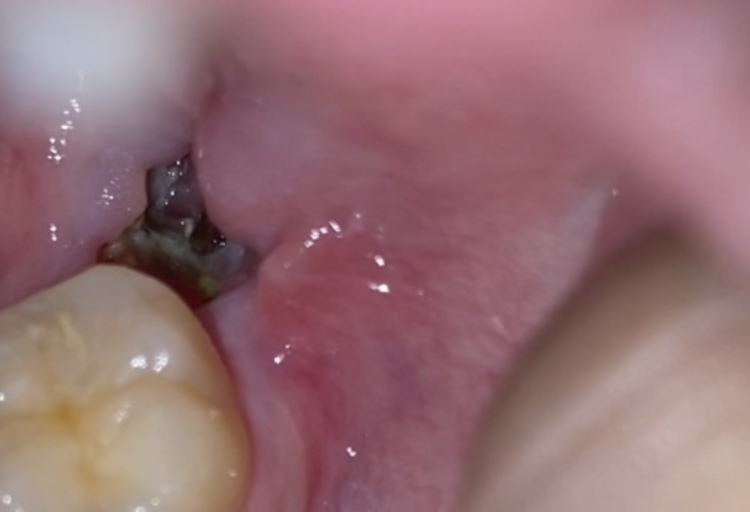

So I have dry socket? Is it infected or healing well? 9 days after wisdom tooth extraction

Hi!! This is my first ever tooth extraction, I’m wondering if I have dry socket ? Or an infection? Or is it healing normally? It’s been 9 days since having my impacted wisdom tooth removed. The place I went to really didn’t give me any information...